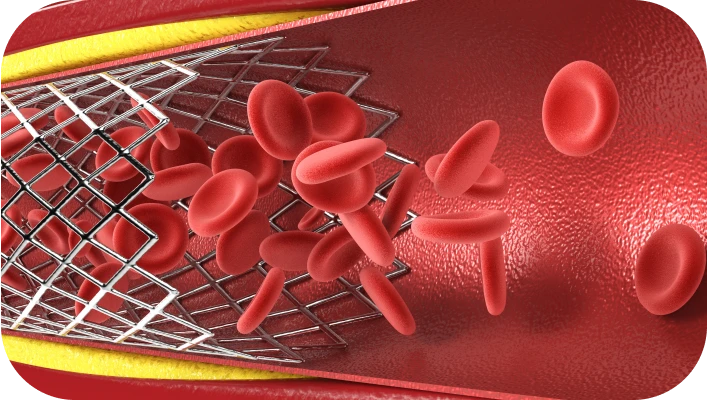

- Blood vessels become

stronger and more elastic - Reduces strain on the heart and

helps fight high blood pressure - Improves circulation, supplying the

brain and vital organs with oxygen

Vasculidon is designed to help your body fight high blood pressure and maintain the vessels are in excellent shape. Each ingredient is natural, clinically studied and works in synergy: strengthens blood vessels, maintains normal blood pressure and improves blood circulation.

- The vessels remain elastic and strong, reducing the load on the heart

- Blood circulation improves, increasing energy and overall well-being

Vasculidon helps to clear blood vessels of excess cholesterol, makes them more elastic, reduces stress on heart and improves blood circulation. Thanks to this, the brain and organs receive more oxygen, and you feel cheerfulness and lightness. Every day gives you confidence that your blood pressure is under control and your heart health is in safe hands. First you will notice the results in a few days.*